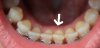

Nun aber mal wieder ein paar Vergleichsbilder zum Aufheitern:)

- Einmal die Seitenansicht, wo man die Bisshebung sieht

- Und einmal ein Vergleich von vorher ohne Spange zu heute. Front, UK und Seitenansicht. Hier sieht man gut wie viel sich getan hat v.a. auch im Biss selbst. Kein Tiefbiss mehr und die Verzahnung rechts hat sich enorm eingependelt (auf dem Bild sieht es so aus als hätte ich vorher mit den Backenzähnen nicht wirklich zusammengebissen, kann mich ehrlich gesagt nicht mehr mal dran erinnern)

(Die Verfärbungen bitte ignorieren, die sind nicht so schick...)

Eine Sache hab ich zwar schon beim KFO angesprochen aber er meinte "das passt so". Daher wollte ich mal kurz hier nachfragen. Beim Einzelbild von den UK Schneidezähnen... ist der 31er (weißer Pfeil) für euch gerade? Er war vorher mit der Kante zum 41er (dieser hat eine Komposit Spitze da als Kind ein Eck abgebrochen ist) ziemlich nach innen, also in die Mundhöhle, gedreht und hat sich ein gutes Stück gerade gedreht. Aber ich finde die Oberkante des Zahns ist nicht 100%ig in einer Linie mit dem Rest. Ich verstehe, dass es vielleicht grad einfach am Platz mangelt und eigentlich verlange ich nicht, dass alle Zähne 100% kerzengerade sind aber ich denke mir halt, dass er sich ansonsten wieder leicht in die alte Position dreht, wenn er v.a. nicht mit dem 41er in einer Linie ist!? Hoffe man versteht, was ich meine...

Achja: Habe im Moment wieder eine kleine Lücke zwischen 11er und 12er. Sie wurde zwar schon mal mittels Powerchain geschlossen, aber ich denke es liegt bissi daran, dass der 12er etwas "eingekerbt" (meine Schuld) und nicht so breit wie der 22er ist. Mal sehn was daraus wird